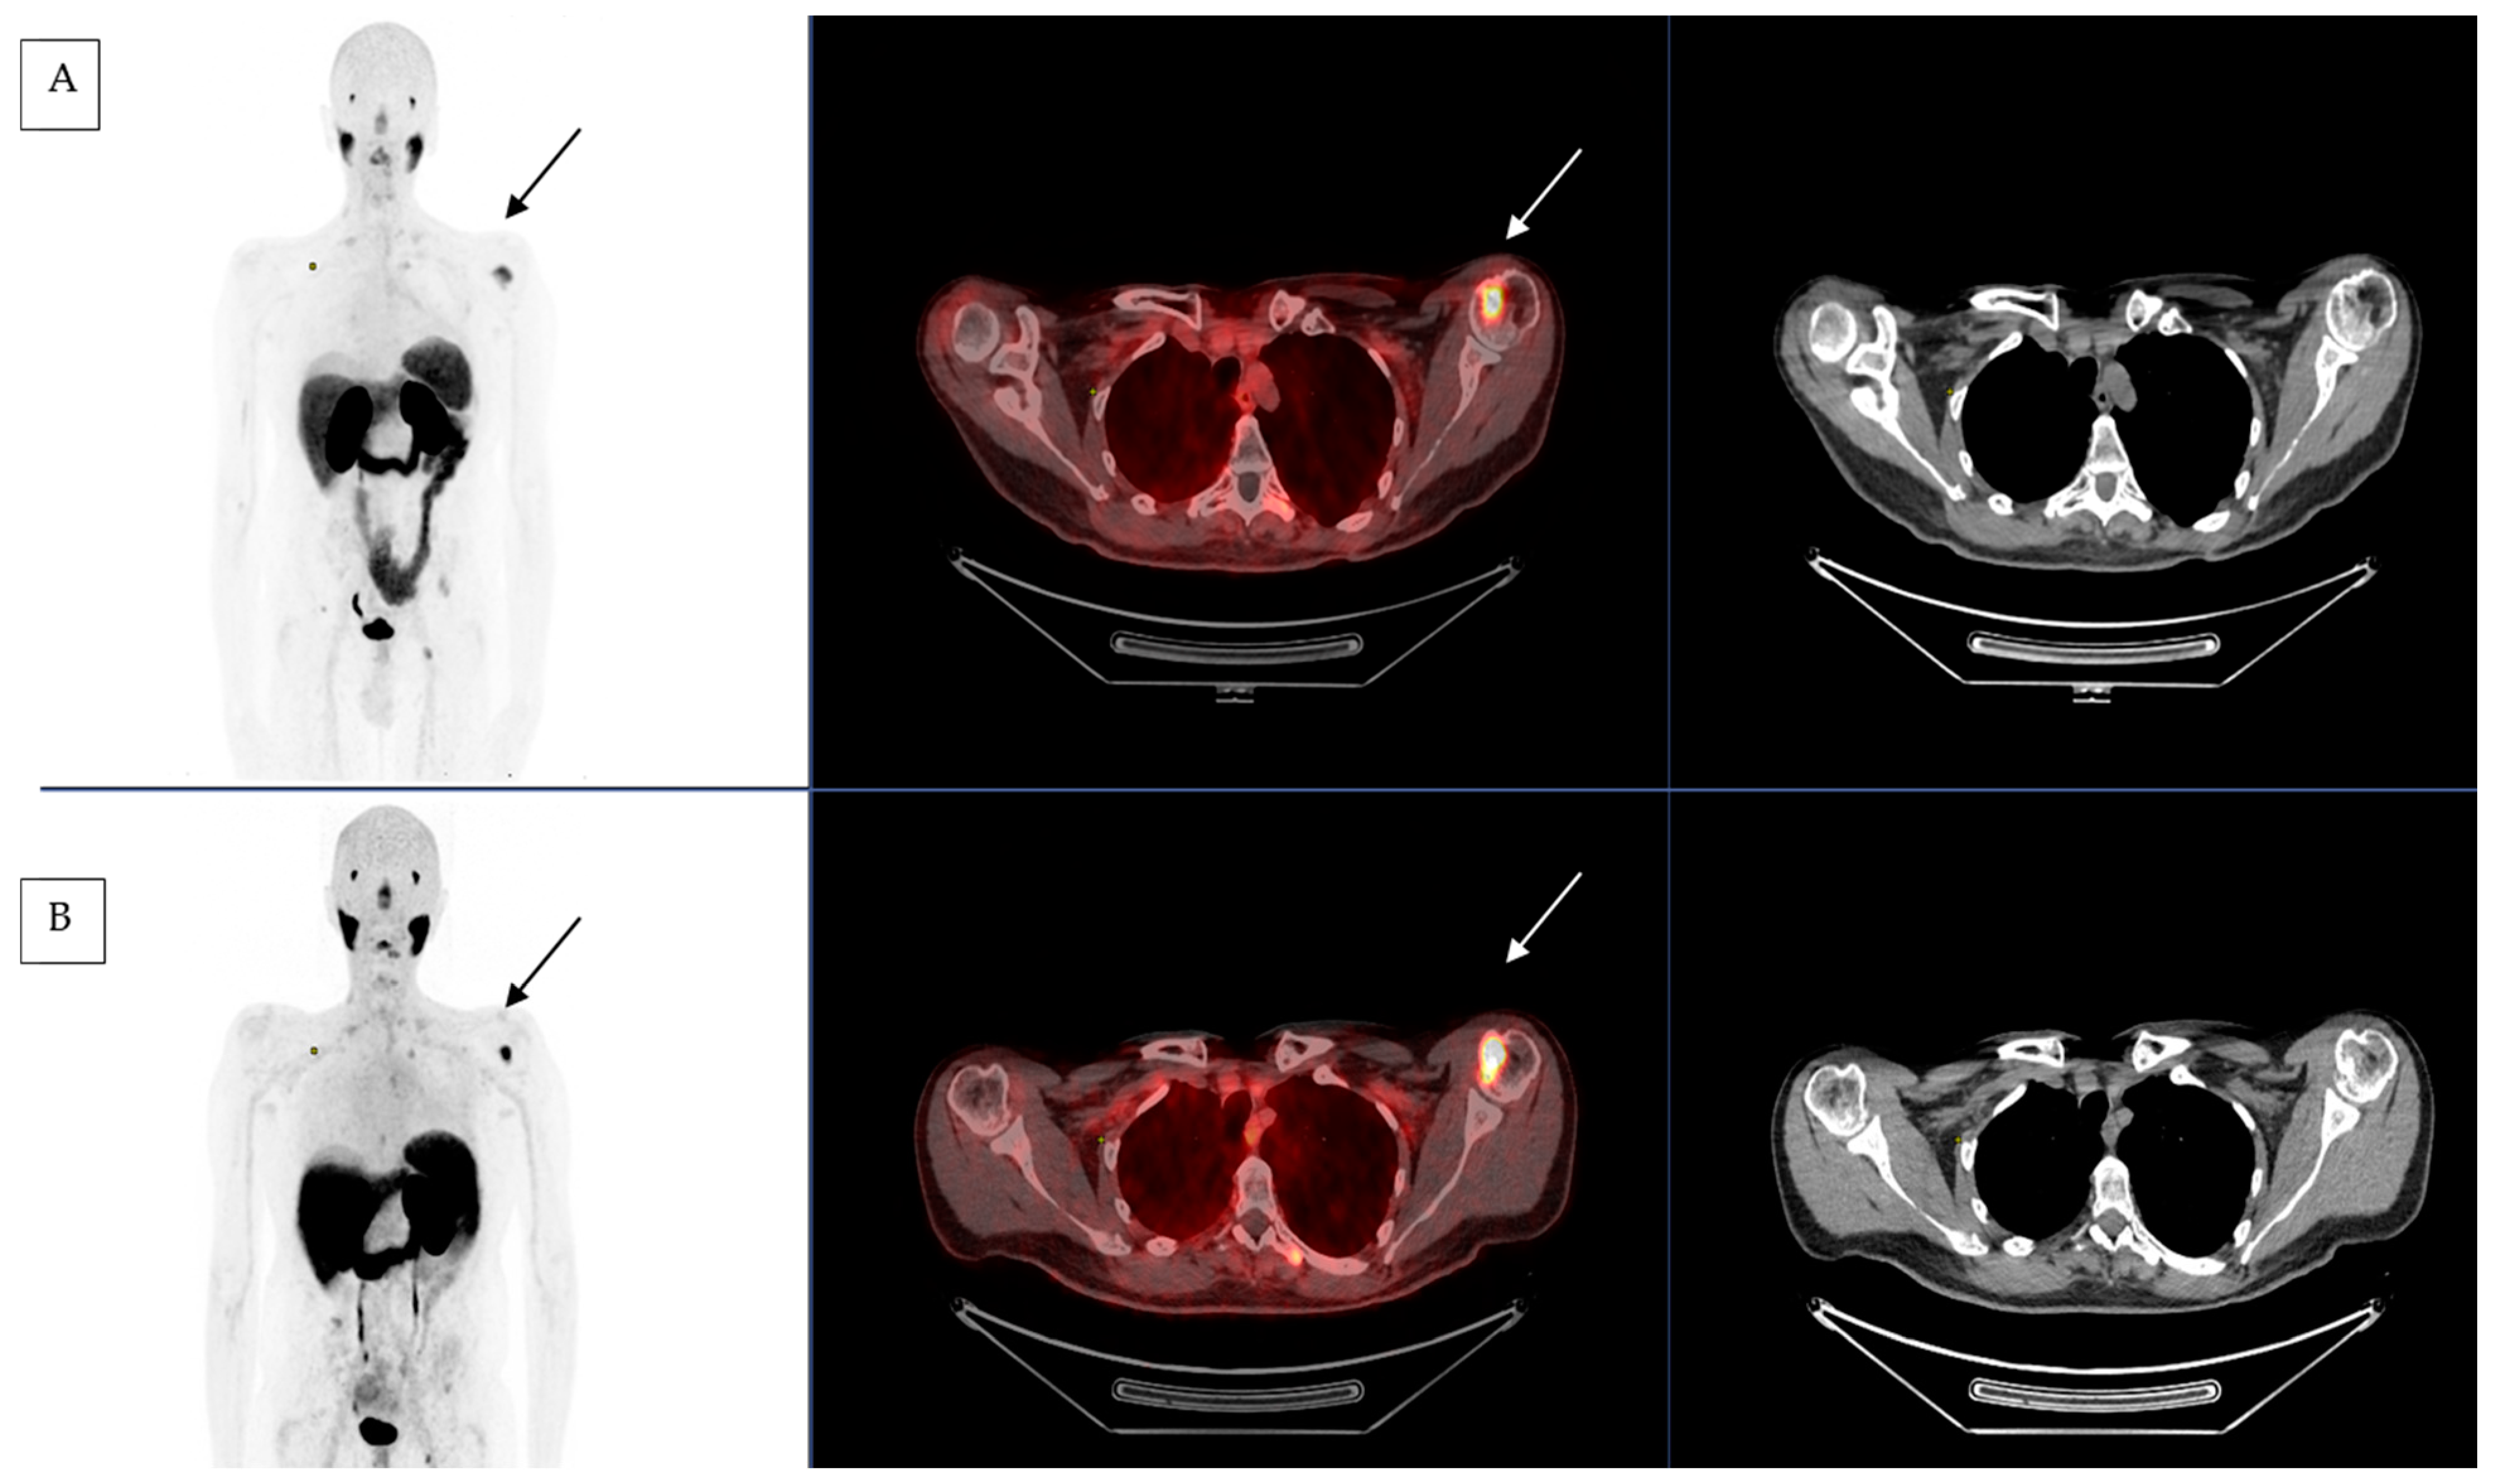

2.2. [177Lu]Lu-PSMA-617 Therapy Used in Salivary Gland Cancer

2.3. First Compassionate Use of [177Lu]Lu-PSMA-617 in Salivary Gland Cancer in France